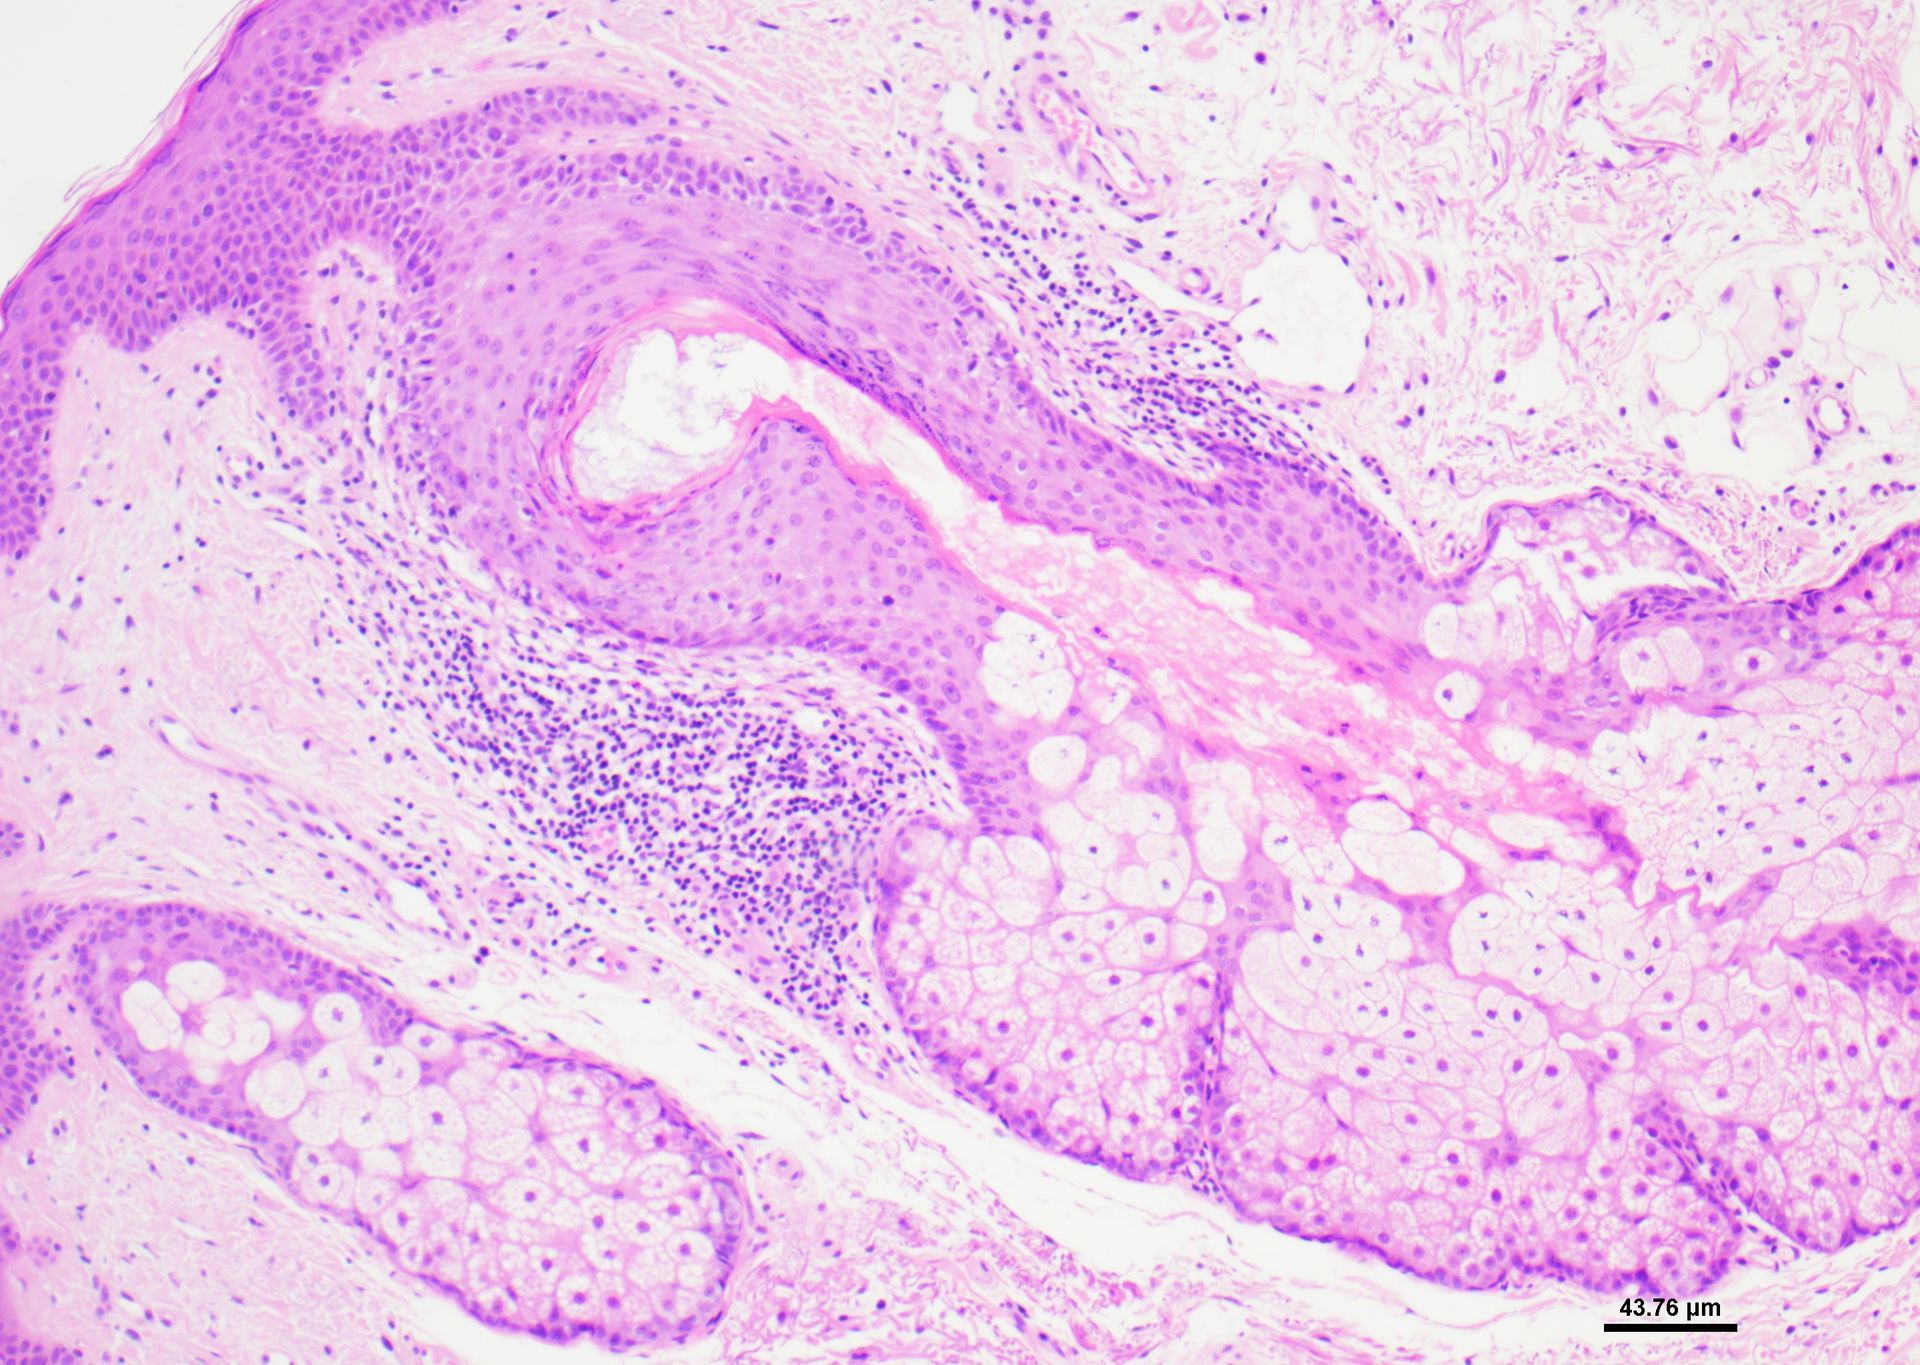

- Diagnostiske halvtynde harpikssnit